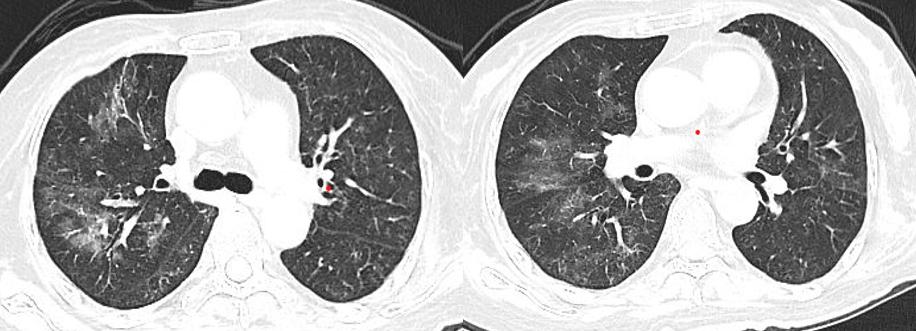

胸部CT(10-23):两肺弥漫斑片影,右肺中叶及左肺上叶部分实变,炎症可能,较前2020-07-03新发。右肺下叶淡斑片影及条索影,考虑慢性炎症/陈旧灶,较前加重。

胸部CT(10-28):两肺弥漫斑片影,右肺中叶及左肺上叶部分实变,炎症可能,较前2020-10-23进展,治疗后复查。右肺下叶淡斑片影及条索影,考虑慢性炎症/陈旧灶,较前相仿。

胸部CT示(2020-11-19):两肺弥漫模糊斑片影,局部实变,较前2020-10-28有所好转。